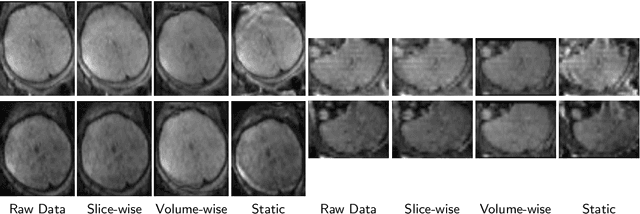

Abstract:Diffusion magnetic resonance imaging (dMRI) is pivotal for probing the microstructure of the rapidly-developing fetal brain. However, fetal motion during scans and its interaction with magnetic field inhomogeneities result in artifacts and data scattering across spatial and angular domains. The effects of those artifacts are more pronounced in high-angular resolution fetal dMRI, where signal-to-noise ratio is very low. Those effects lead to biased estimates and compromise the consistency and reliability of dMRI analysis. This work presents HAITCH, the first and the only publicly available tool to correct and reconstruct multi-shell high-angular resolution fetal dMRI data. HAITCH offers several technical advances that include a blip-reversed dual-echo acquisition for dynamic distortion correction, advanced motion correction for model-free and robust reconstruction, optimized multi-shell design for enhanced information capture and increased tolerance to motion, and outlier detection for improved reconstruction fidelity. The framework is open-source, flexible, and can be used to process any type of fetal dMRI data including single-echo or single-shell acquisitions, but is most effective when used with multi-shell multi-echo fetal dMRI data that cannot be processed with any of the existing tools. Validation experiments on real fetal dMRI scans demonstrate significant improvements and accurate correction across diverse fetal ages and motion levels. HAITCH successfully removes artifacts and reconstructs high-fidelity fetal dMRI data suitable for advanced diffusion modeling, including fiber orientation distribution function estimation. These advancements pave the way for more reliable analysis of the fetal brain microstructure and tractography under challenging imaging conditions.